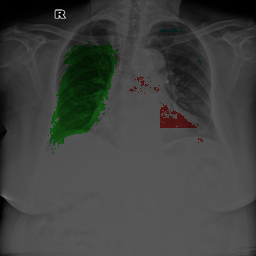

5.1.4 Comparison Under Small-Scale Data

It is worth mentioning that, MBG, IMBP, EL, and VLUU are end-to-end methods, i.e. they do not require any auxiliary NNs or multi-stage training procedures. We provide the qualitative comparison of end-to-end methods in Fig. 6(a). VLUU tends to output more realistic masks than the STOA method EL in terms of the location and shape.